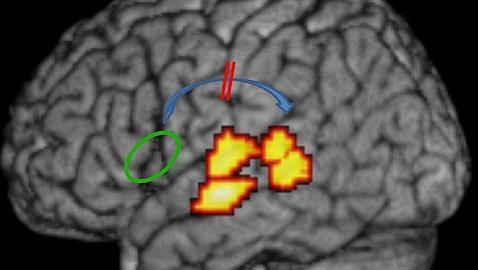

Pero el misterioso origen de la dislexia parece que acaba de ser desvelado. Los artífices de este hallazgo son un equipo de investigadores de la Universidad de Lovaina , en Bélgica, quienes tras analizar las dos teorías vigentes han llegado a la conclusión de que las raíces de la dislexia se encuentran en una conexión deficiente en las representaciones foneticas en el cerebro y no la calidad de dichas representaciones.

Los investigadores han combinado varias técnicas de neuroimagen para analizar a 22 sujetos normales y 23 adultos disléxicos con el fin de desentrañar si la dislexia estaba causada por la mala calidad de las representaciones fonéticas o por la dificultad en el acceso a una representación intacta. Sus resultados indican que las representaciones sonoras del habla están intactas, pero una conexión disfuncional entre las áreas del lenguaje frontal y temporal impide el acceso eficiente a las representaciones. A peor conexión, señala el investigador Maaike Vandermosten, «menor capacidad de realizar las pruebas de escritura, lectura y aprendizaje a las que se sometieron los voluntarios». «Piensen en una serie de ordenadores en red; durante mucho tiempo se ha pensado que en la dislexia lo que ocurre es que la información almacenada en el servidor está degradada, pero en realidad no es así. La información está intacta, lo que falla es la conexión para acceder a la información, que es demasiada lenta o está dañada», explica Bart Boets, coordinador del trabajo.

Las actuales terapias dirigidas para la dislexia está diseñadas para mejorar la calidad de estas representaciones, comenta otro de los investigadores, Hans Op de Beeck. «La buena noticia es que dichas intervenciones también deben mejorar esta calidad de acceso. Pero además –añade-, con el conocimiento actual podríamos en el futuro diseñar intervenciones más focalizadas y efectivas que se dirijan específicamente a mejorar la conexión entre las regiones frontales y temporales del lenguaje». En este sentido, Boets considera que algunas técnicas innovadoras no invasivas de estimulación cerebral, como la estimulación magnética transcraneal, podrían ser utilizadas.